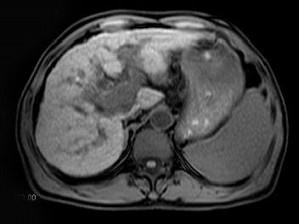

问题 男,65岁。右上腹部疼痛不适,乏力4月余。AFP升高。MRI如下图所示。应诊断为 ( )

选项 A、转移瘤 B、未见异常 C、胆管细胞癌 D、肝腺瘤 E、肝右叶肝细胞癌并门脉癌栓形成

答案 E